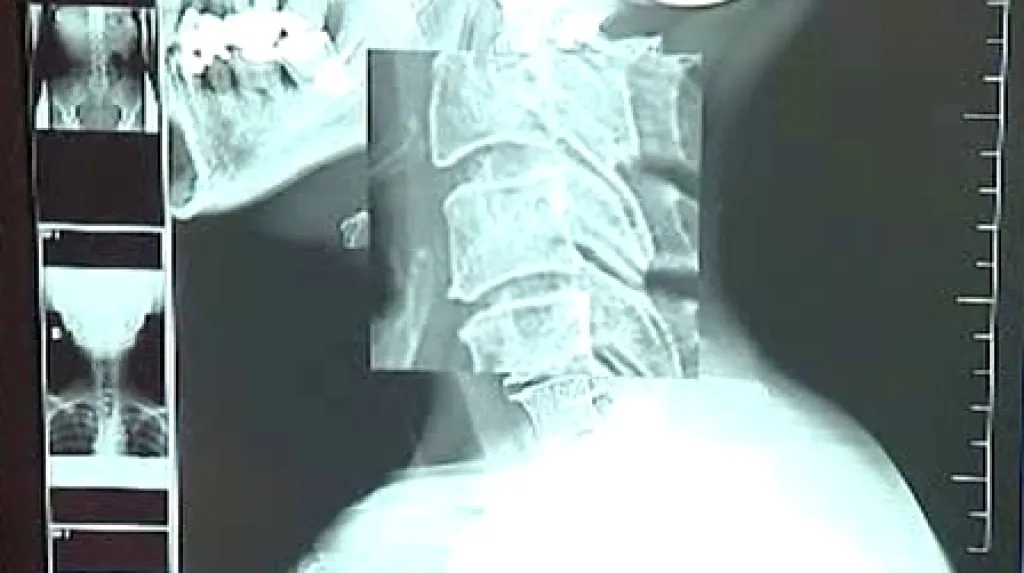

Mezi nejvýraznější pozitiva nového rentgenu patří nesrovnatelně lepší kvalita zobrazení, přesnost a rychlost. „Jedním kliknutím myši si můžu obrázek zmenšit nebo zvětšit, bez ztráty kvality samozřejmě,“ uvedl primář radiodiagnostického oddělení polikliniky MephaCentrum František Otáhal. Rentgenový snímač navíc u pacienta o polovinu snižuje radiační zátěž.

Lékaři se na monitoru zobrazí informace o stavu pacienta za pět vteřin po ukončení snímkování, diagnózu tak může ihned konzultovat se specializovanými pracovišti. „Prakticky se můžeme spojit s celou republikou nebo dokonce s celým světem,“ pokračoval Otáhal.